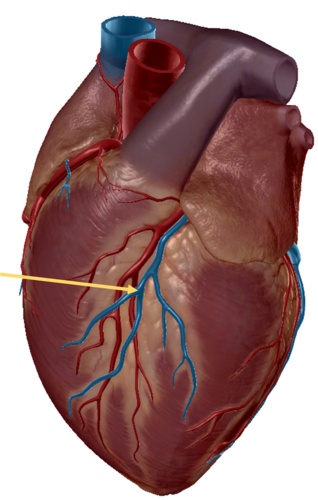

great cardiac vein

middle cardiac vein

coronary sinus

anterior inter ventricular artery

posterior interventricular sulcus